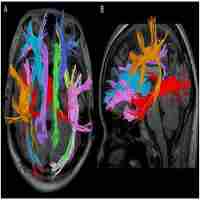

| Abstract | BACKGROUND: The brainstem is the main region that innervates neurotransmitter release to the Hypothalamic-Pituitary Adrenal (HPA) axis and fronto-limbic circuits, two key brain circuits found to be dysfunctional in Major Depressive Disorder (MDD). However, the brainstem's role in MDD has only been evaluated in limited reports. Using Diffusion Tensor Imaging (DTI), we investigated whether major brainstem white matter tracts that relate to these two circuits differ in MDD patients compared to healthy controls. METHODS: MDD patients (n = 95) and age- and gender-matched controls (n = 34) were assessed using probabilistic tractography of DTI to delineate three distinct brainstem tracts: the nigrostriatal tract (connecting brainstem to striatum), solitary tract (connecting brainstem to amygdala) and corticospinal tract (connecting brainstem to precentral cortex). Fractional anisotropy (FA) was used to measure the white matter integrity of these tracts, and measures were compared between MDD and control participants. RESULTS: MDD participants were characterized by a significant and specific decrease in white matter integrity of the right solitary tract (p<0.009 using independent t-test), which is a "bottom up" afferent pathway that connects the brainstem to the amygdala. This decrease was not related to symptom severity. CONCLUSIONS: The results provide new evidence to suggest that structural connectivity between the brainstem and the amygdala is altered in MDD. These results are interesting in light of predominant theories regarding amygdala-mediated emotional reactivity observed in functional imaging studies of MDD. The characterization of altered white matter integrity in the solitary tract in MDD supports the possibility of dysfunctional brainstem-amygdala connectivity impacting vulnerable circuits in MDD. |